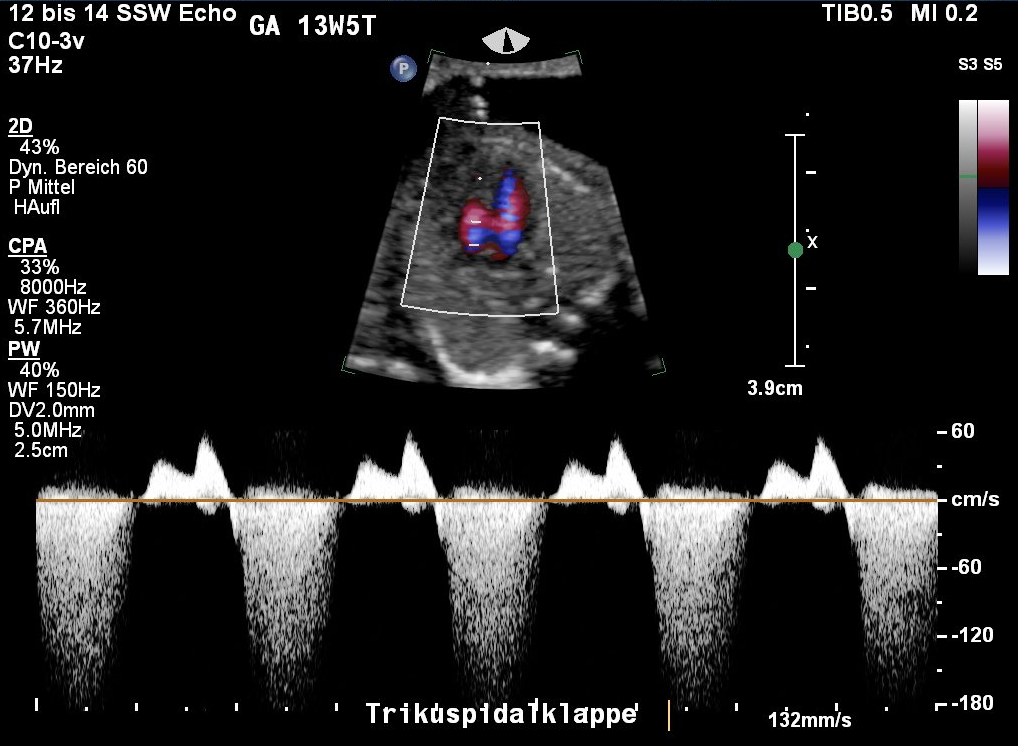

Zwei weitere Marker sind dopplersonographische Untersuchungen. Bei der Kontrolle des Blutflusses über

eine Herzklappe zwischen rechten Vorhof und rechter Herzkammer, Trikuspidalklappe

genannt, wird nach einer Trikuspidalklappenregurgitation (TK) gesucht, einem unzureichenden Klappenverschluss. Physiologischerweise zeigt sich über dieser Herzklappe kein Rückfluss in der Systole, der Blut-Ausströmungsphase des Herzens. Ein Regurgitation liegt definitionsgemäß vor, wenn der Rückfluss mit einer Spitzengeschwindigkeit von mindestens 60 cm/s die Hälfte der Systole betrifft. Dieser liegt bei Feten ohne Chromosomenstörung in 1 % der Fälle

vor, bei Feten mit Trisomie 21 in 65 % der Fälle.

Unauffälliger Fluss über die Trikuspidalklappe